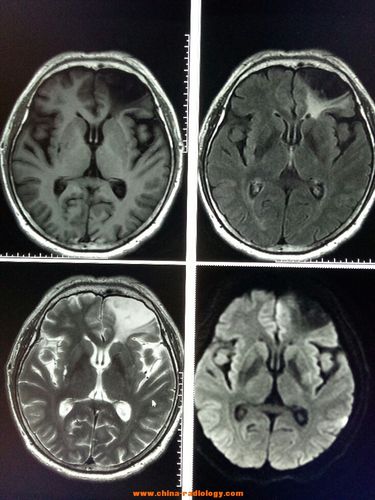

脑白质病变影像诊断

脑白质病变

脑白质变性

脑白质高信号

轻度脑白质变性

脑白质缺血性改变

缺血性脑白质病变

脑白质脱髓鞘病变

脑白质脱髓鞘CT